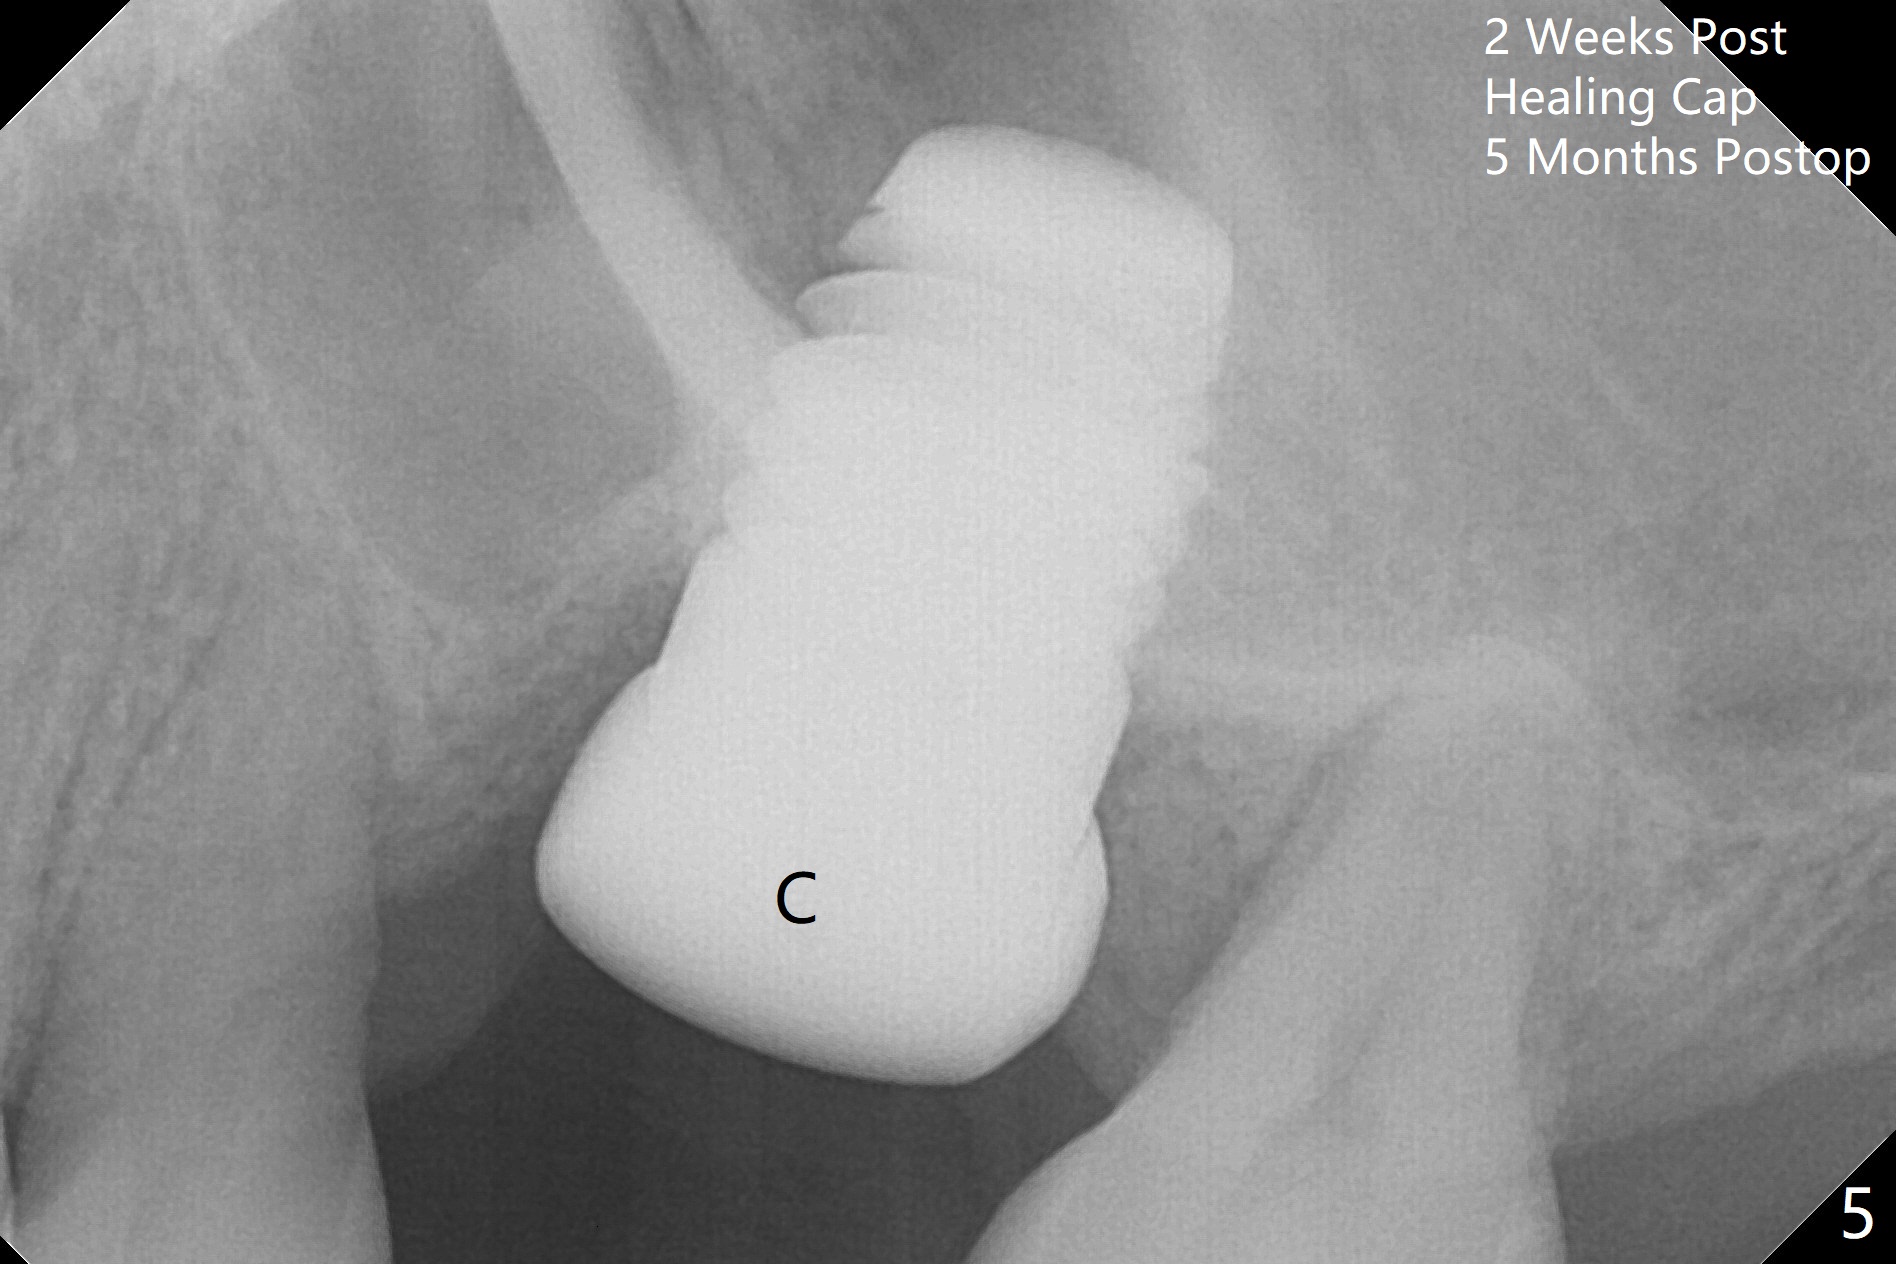

Three months post cementation, the implant at #14 is found loose (Fig.1: 6.5x11 mm) and removed. After removal of minimal granulation tissue, normal saline disappears into the apical end of osteotomy. In fact there is no bone apically, although the sinus membrane is intact. After try in of various taps (tapered and cylindrical, bone- and tissue-level), a 8x14 mm dummy implant is placed (Fig.2), followed by Osteogen plug and the same sized definitive implant, which has to be placed deeper to obtain ~ 45 Ncm (Fig.3). There is minimal thread engagement. If the implant fails, place 2 layers of PRF membrane apically, bone graft and 1 layer of PRF coronally for ridge preservation. A healing abutment will be placed to expose the coronal end of the implant ~ 4 months postop. The tissue-level implant remains subgingival 4.5 months postop (Fig.4). A 8 mm healing cuff cannot be placed even after laser gingivectomy. The implant is 2 mm subcrestal mesially. Torque wrench cannot reverse the implant at 60 Ncm. The implant is later reversed with Tatum wrench until it is turned with the torque wrench at 30 Ncm. The implant remains stable, while the healing cuff with Triple Antibiotic Ointment is placed. The healing cuff is stable 2 weeks later (Fig.5 C). With progressive loading for a month, a crown is cemented 9 months postop. There appears no bone loss 2.5 months post cementation (11 months postop, Fig.6). Return to Upper Molar Immediate Implant, Armaments, IBS #3 Xin Wei, DDS, PhD, MS 1st edition 04/30/2018, last revision 04/14/2019